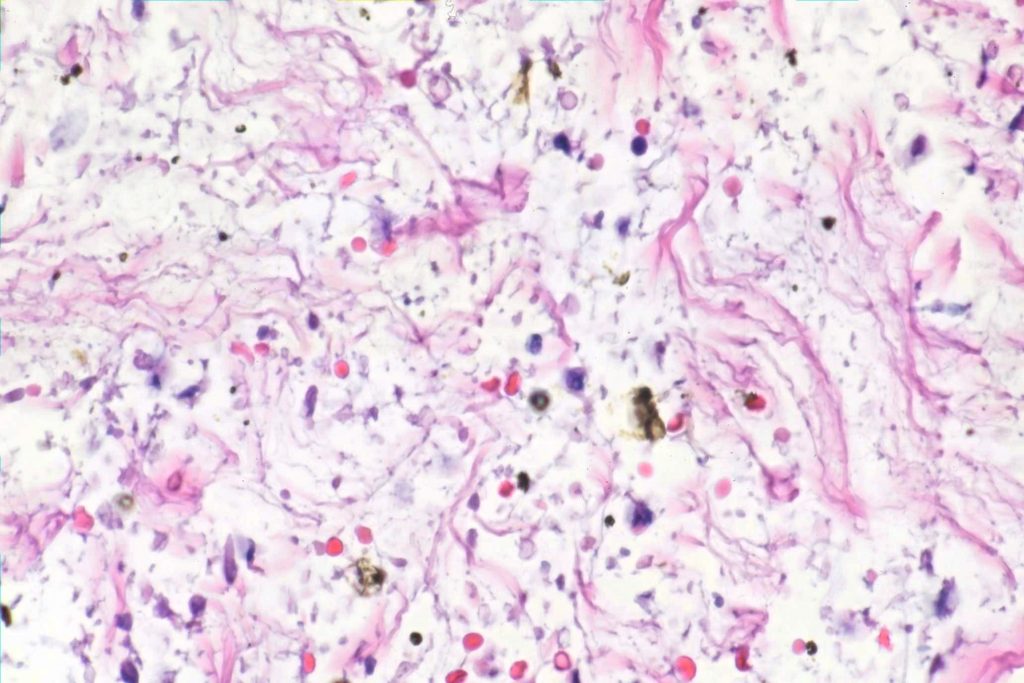

Here are some close shots of gunk in the lymphatics.

Note the pigmented debris. Here are more closeup shots:

The pigmented debris are largely birefringent:

This is consistent with fecal material.